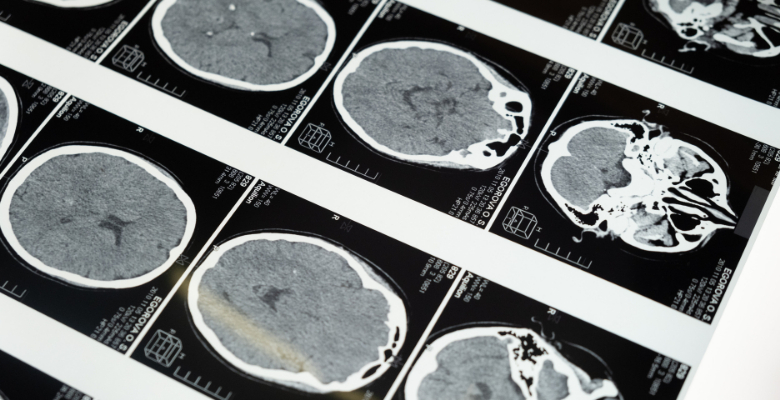

Um novo estudo realizado pela University of Oxford concluiu que a COVID-19 causa perda de massa cinzenta em várias partes do cérebro, pode comprometer a memória olfativa a longo prazo e contribuir para o desenvolvimento da doença de Alzheimer.